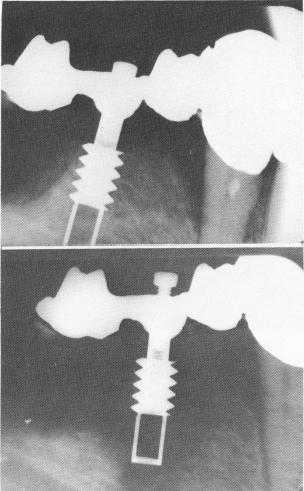

How just one uncompensated divergence from the list of implant design and insertion requirements can result in failure is summarized in Fig. 14-6. In A several implant designs are shown just after insertion. All are screw-type implants. Most are made of metal, but one is made of synthetic sapphire, all of which are known to be biologically inert materials. All were splinted for security, but B and C show what usually happens when a solid screw type implant with an unrestricted neck is used. Even though

broad-necked implants may be successful in some cases, there is a tendency for bone breakdown to occur with this type of design, no matter of what material it is constructed.

Proof that an unrestricted neck and a solid body in an implant can cause bone breakdown is shown in Fig. 14-7. To ensure that these particular design features, not the material of which the implant was made, caused the failures, Linkow coated several of his implant designs yv ith synthetic sapphire. Bone breakdown did not occur.